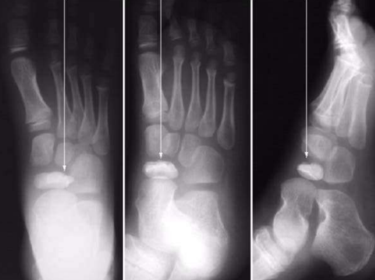

| What type of fracture is shown at the 2nd metatarsal? | Transverse fracture |

| What type of fracture is this? | Oblique fracture |

| What type of fracture is this? | Spiral fracture |

| What type of fracture is this? | Comminuted fracture |